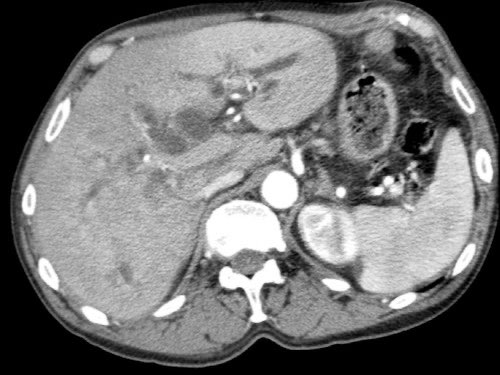

Tái tạo mặt phẳng coronal cho thấy:

- Bất thường bờ viền thành SMV được nhận thấy rõ hơn trên tái tạo coronal này (mũi tên).

- Khối u ở thân tụy (đầu mũi tên trắng).

- Huyết khối trong các nhánh bên của SMV (mũi tên xanh nhỏ).